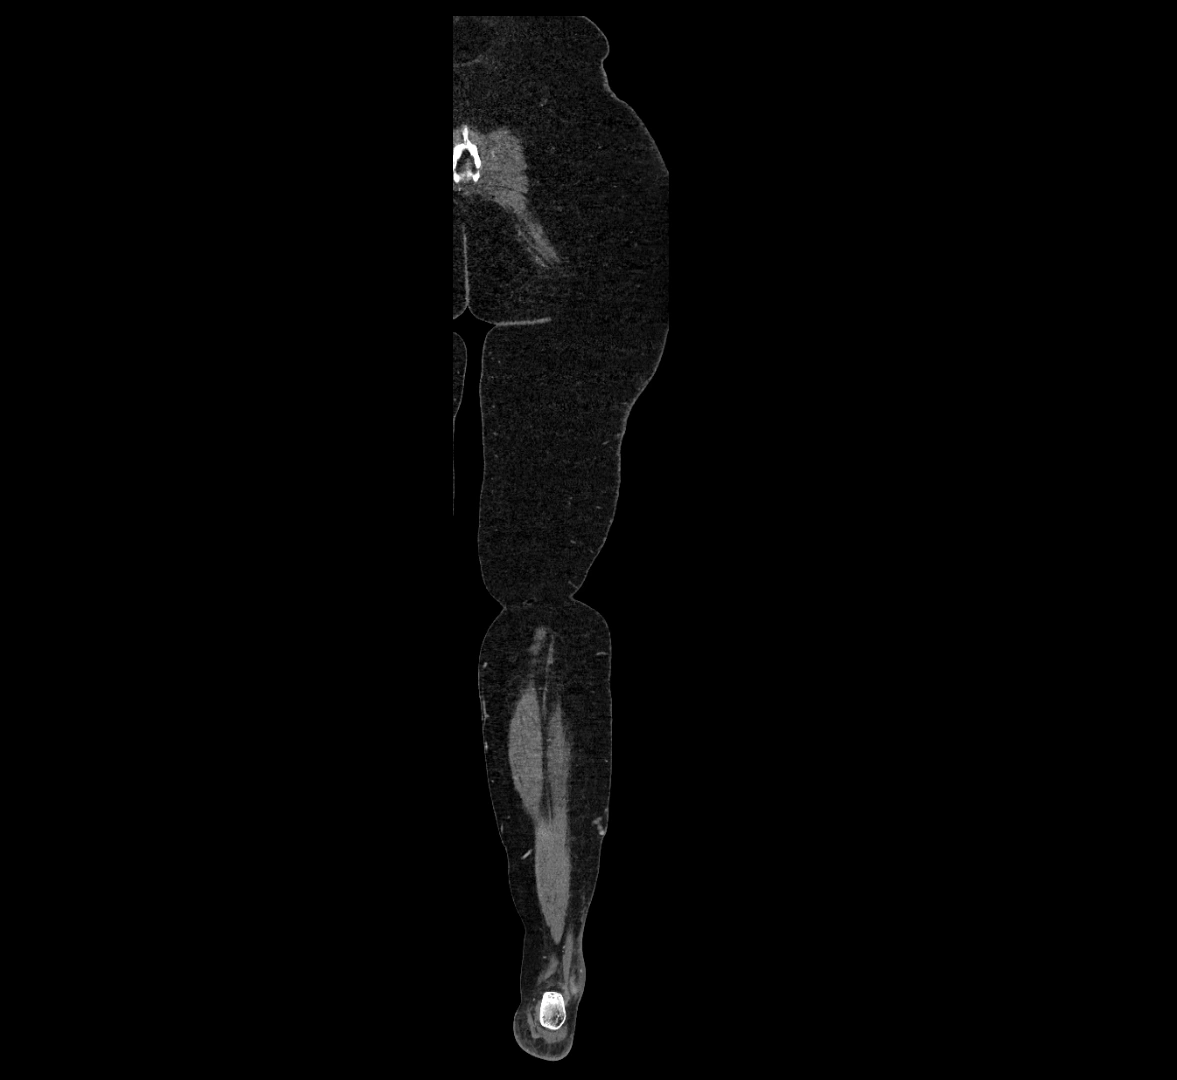

CT images

image